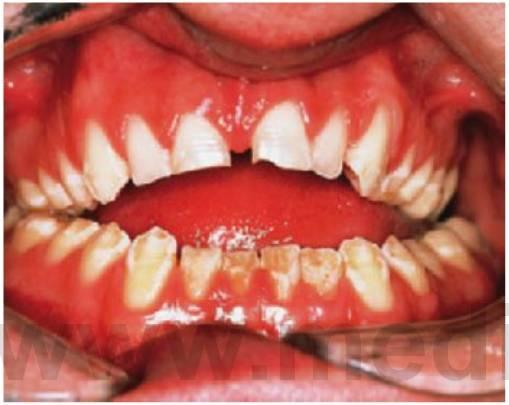

Dentinogénesis imperfecta (OMIm125490)

La dentinogénesis imperfecta es un trastorno hereditario de la dentina que puede ir o no asociado a osteogénesis imperfecta. En ocasiones se utiliza el término «dentina opalescente hereditaria» para este cuadro aislado. Tanto la osteogénesis imperfecta como la dentinogénesis imperfecta se transmiten de forma autosómica dominante, y son indistinguibles en el plano clínico pese a tener una base genética diferente. La osteogénesis imperfecta se debe a mutaciones en los genes del colágeno tipo I, y la dentinogénesis imperfecta a mutaciones en el gen de la sialofosfoproteína dentinaria Algunos individuos y familias con osteogénesis imperfecta pueden presentar signos clínicos de dentinogénesis imperfecta, pero en otras familias puede existir una expresión variable de rasgo. En estas familias, algunos individuos pueden tener una dentina anómala, mientras que los dientes de otros no están afectados. Sin embargo, y debido al mismo defecto del colágeno, todos los niños con osteogénesis imperfecta pueden presentar una anomalía en la dentina en el plano subclínico. Se debe considerar la posible existencia de osteogénesis imperfecta en niños que presentan dentinogénesis imperfecta por medio de pruebas de densidad ósea y, así, la presencia de escleróticas azules o una historia de fracturas óseas debería alertar al especialista de la posibilidad de una osteogénesis imperfecta (fig. 9.29).

Manifestaciones dentales

- Opalescencia o decoloración ambarina, entre gris y azul-púrpura (fig. 9.29)

- Obliteración pulpar (fig. 9.29D).

- Coronas relativamente bulbosas.

- Raíces cortas y estrechas.

- El esmalte tiende a perderse después de la erupción y se expone la dentina blanda, que se desgasta rápidamente, lo que podría deberse a la debilidad inherente de la dentina más que al defecto del esmalte o a la anomalía en la unión amelodentinaria.